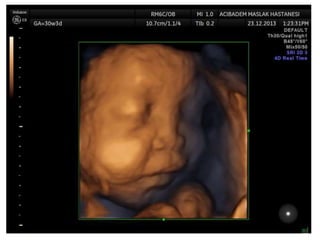

Arthrogryposis

•Multiple congenital joint contractures/ankyloses

involving two or more body areas

•Pena Shokeir phenotype

micrognathia, multiple contractures, camptodactyly

(persistent finger flexion), polyhydramnios

*many are AR

*Lethal due to pulmonary hypoplasia

Arthrogryposis •Multiple congenital jointcontractures/ankyloses involving two or more body areas •Pena Shokeir phenotype micrognathia, multiple contractures, camptodactyly (persistent finger flexion), polyhydramnios *many are AR *Lethal due to pulmonary hypoplasia • Distal arthrogryposis Subset of non-progressive contractures w/o associated primary neurologic or muscle disease